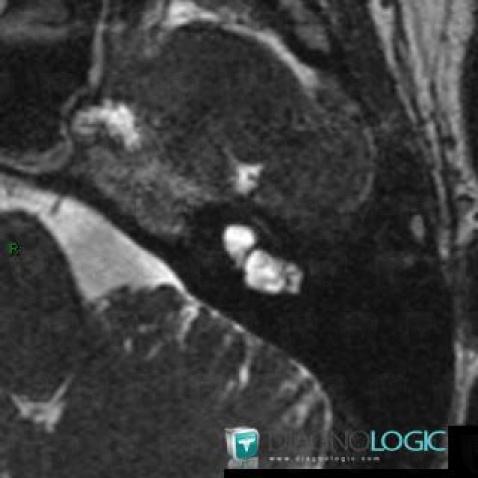

Voici les informations spécifiques à l'image clé ci dessus:

- Diagnostic Dysplasie cochléaire, Localisation(s) Oreille interne, comportant les gammes Lésion de l'oreille interne